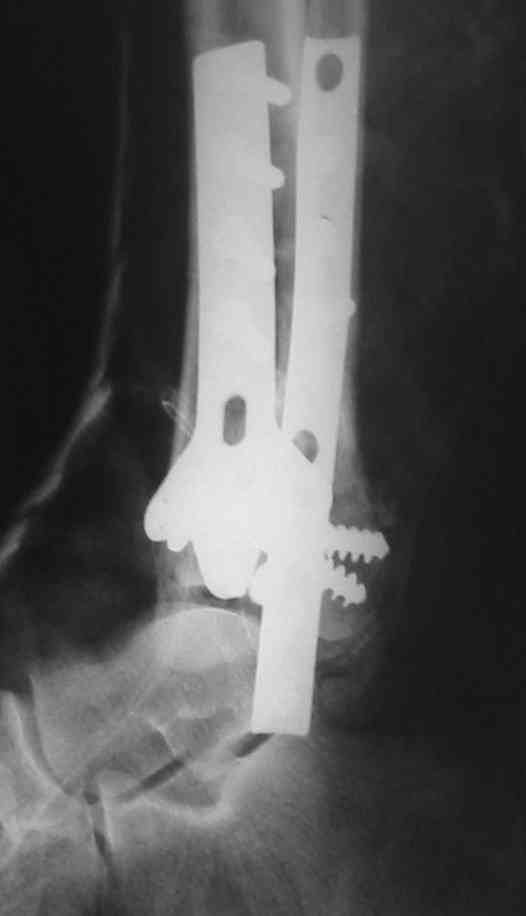

Посмотрим вроде прошло если понравится напишите расскажу как это сделать.По принципам АО кстати при поступлении сначала восстанавливают длину малоберцовой кости фиксируют пластиной 1/3 трубки потом накладывают аппарат наружной фиксации и через 7-10 дней открыто восстанавливают большеберцовую кость.С уважением Дрягин

На рентгенограммах типичный перелом пилона по типу С-3. есть опыт до 100 открытых опреаций у нас в клинике. 20 примерно в год. Принцип один -все внутрисуставные переломы нуждаются в открытой репозиции и внутренней стабильной фиксации. При поступлении КТ не надо, так как получается только нагромождение костей. Истинной картины нет. Главное восстановить длину малоберцовой кости - это ключ к успеху. При поступлении меньше всего надо думать о сосудистых расстройствах, т.к. сама операция и репозиция даже сначала частичная даёт улучшение сосудитых нарушений. Причём очень быстро. Операция в 2этапа. При поступлении доступ позади наружной лодыжки, причём обязательно. После этого репозиция малоберцовой кости и фиксация пластиной 1/3 трубки под винт 3,5. Дренаж и любой аппарат наружной фиксации. Затем после спадения отёка на 5-7-10 день аппрат снимается и дугообразный разрез спереди от медиальной лодыжки 10-12 см. Главной чтобы расстояние между 1 и вторым разрезом было не меньше 7-8 см. Тогда не будет некрозов лоскутов. Таранная кость используется как матрица на неё укладываются отломки и фиксируются пицами. Ренг-контроль. Отломки лежат все отдельно, но ничего не высыпется. При переломах С-3 всегда нужна костная пластика (из крыла). Фиксация пластиной лист клевера простой или LCP. Гипс не нужен. Дренаж до 48 часов. Операция длится 3-4 часа обязательно без жгута. Посылаю примерно такой же случай.

Посылаю результат лечения предыдущего больного через год.

С уважением Дрягин